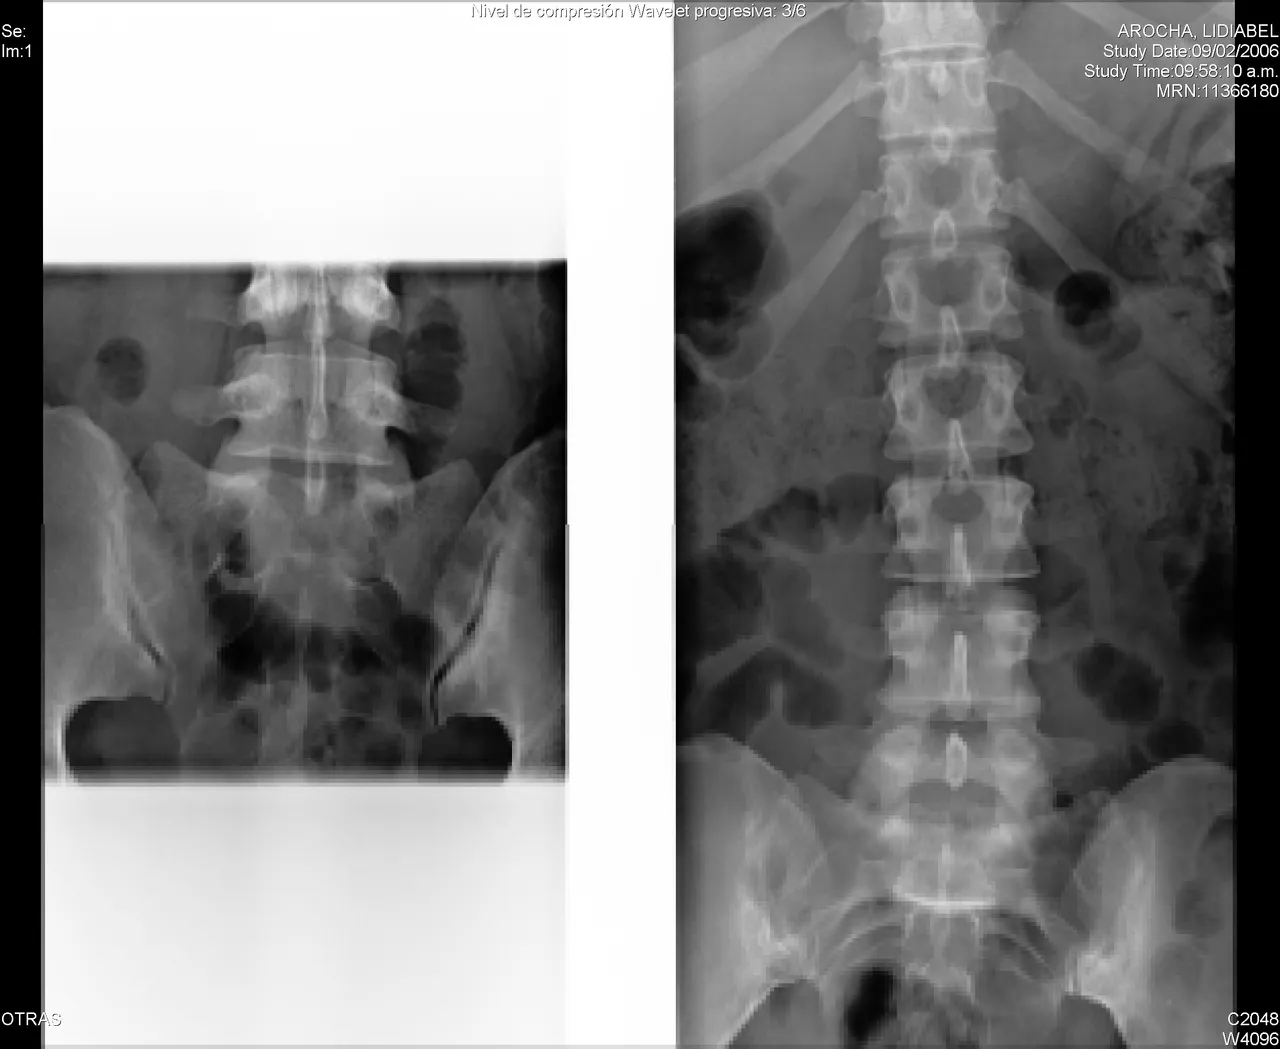

A spinal fracture (spinal compression fracture) occurs when one of the bones in the spine fractures or collapses.

These fractures occur most often in the fifth vertebra of the spine or lumbar spine, although they can also occur in the fourth lumbar vertebra. Fractures may occur on one or both sides of the pars bones. In more severe cases, spondylolisthesis may develop. This occurs when a fractured pars bone separates, allowing the injured vertebra to move forward.

Multiple fractures in the spine can also cause postural changes or a Dowager's hump. If you have lost height or have a Dowager hump, you should consult your physician.

Report any new or unusual back pain to your doctor right away. Early diagnosis can lead to more treatment options. A physical exam, along with an x-ray, can help determine whether or not you have a spinal fracture.

Unfortunately, having a spinal fracture greatly increases your chances of having another one. Over time, multiple fractures can affect the alignment of your spine and cause it to lean forward (Dowager's hump).